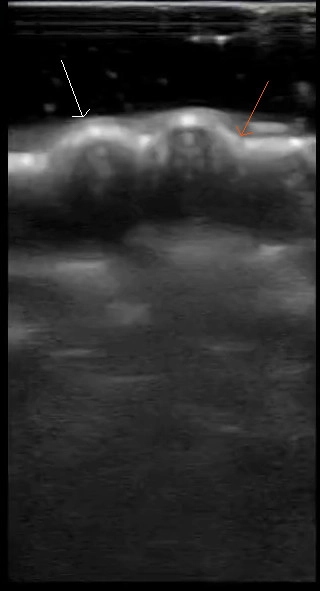

In letzter Zeit erscheinen vermehrt Publikationen in der Zahnheilkunde, z.B. zur Darstellung parodontaler (Abb. 6) [12] oder peri-implantärer Gewebe [13] als auch für die Darstellung periapikaler Läsionen [14–16]. Hierbei werden kleine Linearschallköpfe verwendet (Abb. 7), die aufgrund ihrer geringen Größe gut in der Mundhöhle platzierbar sind. Mit höherer Schallfrequenz sinkt die Eindringtiefe, allerdings bei steigender Ortsauflösung, sodass auch Anwendungen im Bereich der Mundschleimhautdiagnostik analog zu ähnlichen dermatologischen Anwendungen [17] gut vorstellbar sind. Ebenso werden Anwendungen in der Kieferorthopädie (Winkelmessungen [18]) und der Oralchirurgie beschrieben [19–21]. Ein aktueller Review schlussfolgert, dass es ein breites Anwendungsspektrum für Sonographie in der Zahn-, Mund- und Kieferheilkunde gibt [22].